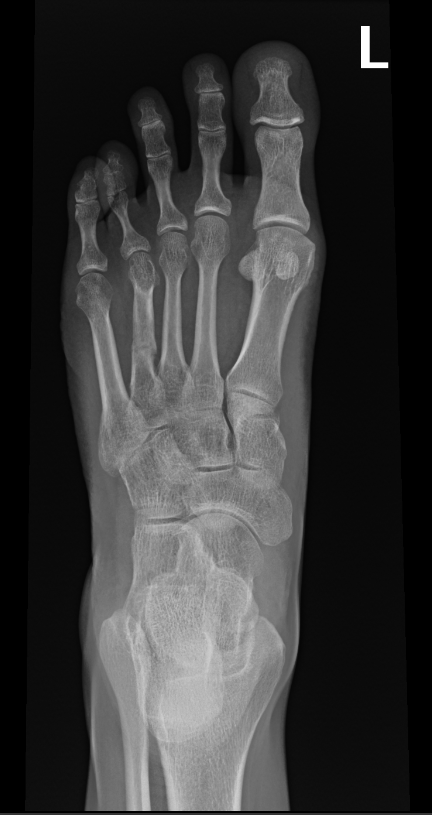

The surgeon in preparation for each surgery preconstructs a customized apparatus. Using wires or pins, the apparatus is surgically attached to the affected limb. Surgery is usually performed percutaneously through small incisions. Special care is taken to minimize injury to the bone and surrounding soft tissue, nerves and blood vessels when making specialized bone cuts.

During the adjustment phase the patient is followed up in the rooms every two weeks with clinical examination and x-rays. A close scrutiny is maintained to identify any complications early.

During the adjustment phase, the patient is followed up in the rooms every two weeks with clinical examination and x-rays. Close scrutiny is maintained to identify any complications early.

After the desired length has been achieved and the limb has been straightened, no further adjustments are made. The apparatus is left in place to allow the new bone to harden and mature. Once the new bone is judged to be sufficiently strong, the frame is removed under a short general anesthetic. A cast or brace may be applied for an additional month or two for further protection. The new bone tissue assumes all the qualities and strength of normal bone with time.